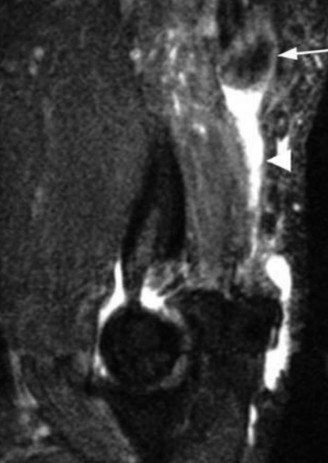

Imaging should include x-rays, which may demonstrate posterior glenoid bone loss or an impaction fracture on the anterior-superior humeral head (Fig. 2–38). CT images with 3D reconstructions can be very useful when assessing the extent of glenoid bone loss and evaluating glenoid and humeral version. Normal glenoid version is from −2 to −8 degrees of retroversion, and this may be increased in posterior instability. MRI can also be useful when assessing the posterior labrum (Fig. 2–39).

Figure 2–39 MRI showing a posterior labrum tear.